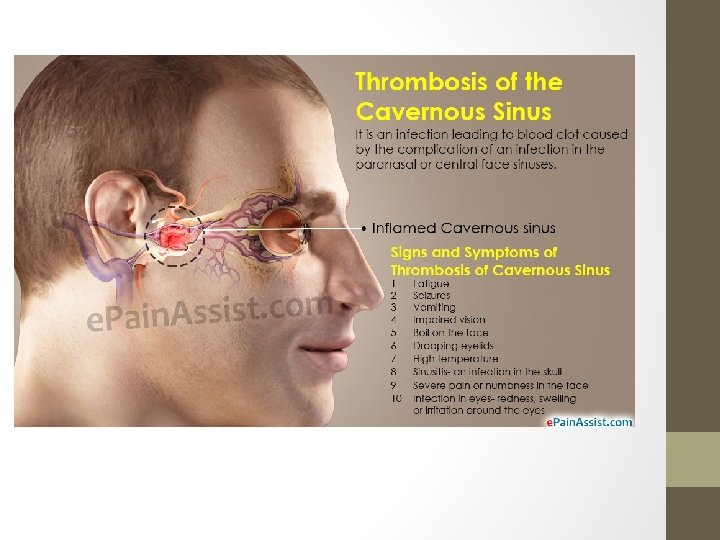

Cavernous Sinus Thrombosis • Rare, high mortality&morbidity Etiology, • Infections: -Most commonly results from contiguous spread of infection from the sinuses or middle third of the face(furuncle), or less commonly dental abscess or orbital cellulitis -Staph. Aureus (%55) • Sinus compression, e. g. trauma, tumour • Procoagulable conditions, e. g. Protein C/S deficiency, OCP use, malignancy • Idiopathic (25%) • Headache(m. common) • focal cranial nerve abnormalities • periorbital edema and visual disturbances